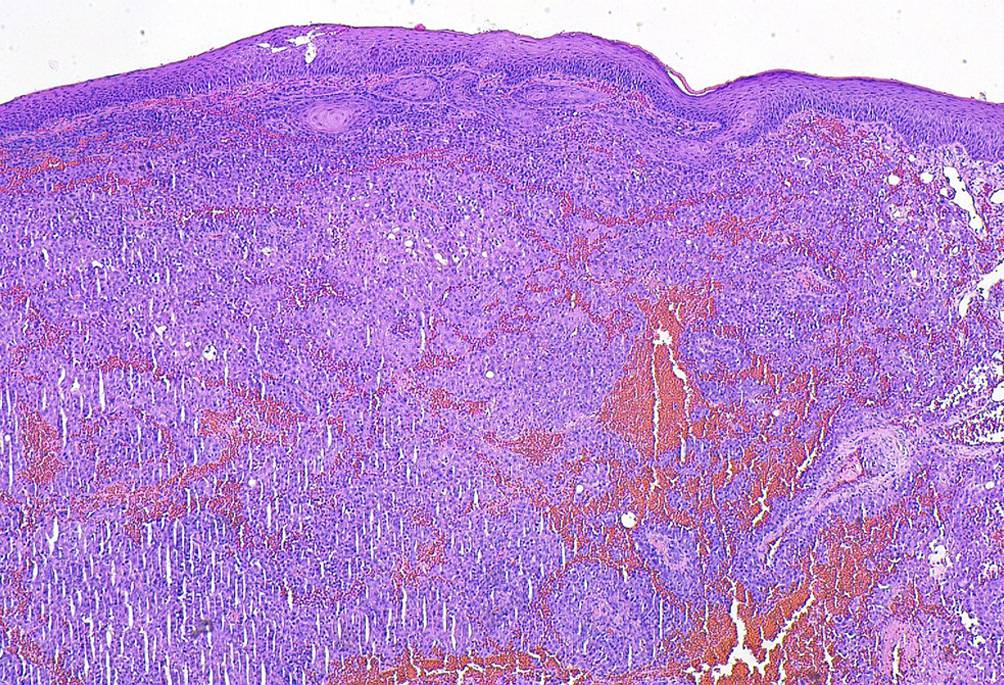

Abb. 2

Hämatoxylin-Eosin-Färbung mit Darstellung eines mehrschichtig verhornten Plattenepithels der Haut. In der darunterliegenden Dermis zeigen sich ausgeprägte interstitielle Blutungen sowie eine Infiltration durch polymorphe, epitheloide, teils diskohäsiv wachsende Tumorzellen (Originalvergrößerung 100:1).